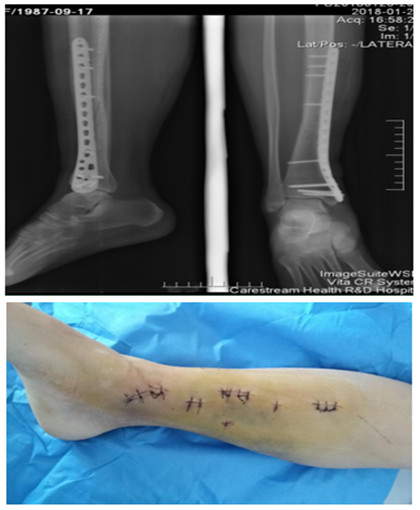

我院首例脛骨骨折MIPPO技術(shù)